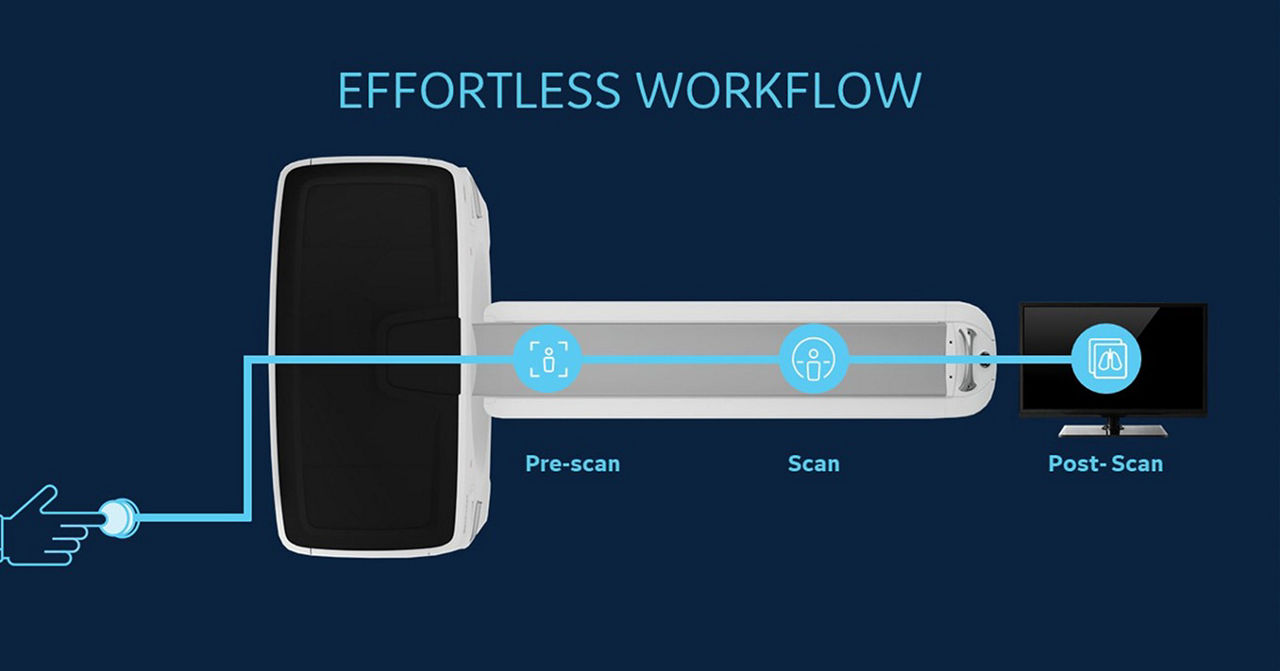

Leveraging transformational imaging technology to realize the promise of precision medicine and help deliver better outcomes. Our medical imaging products range from systems, including MRI, CT, PET, SPECT, Ultrasound, Mammography and X-ray, to digital and AI solutions to help drive healthcare digitialization, help enable faster exam workflow, improve clinical outcomes and increase efficiencies.